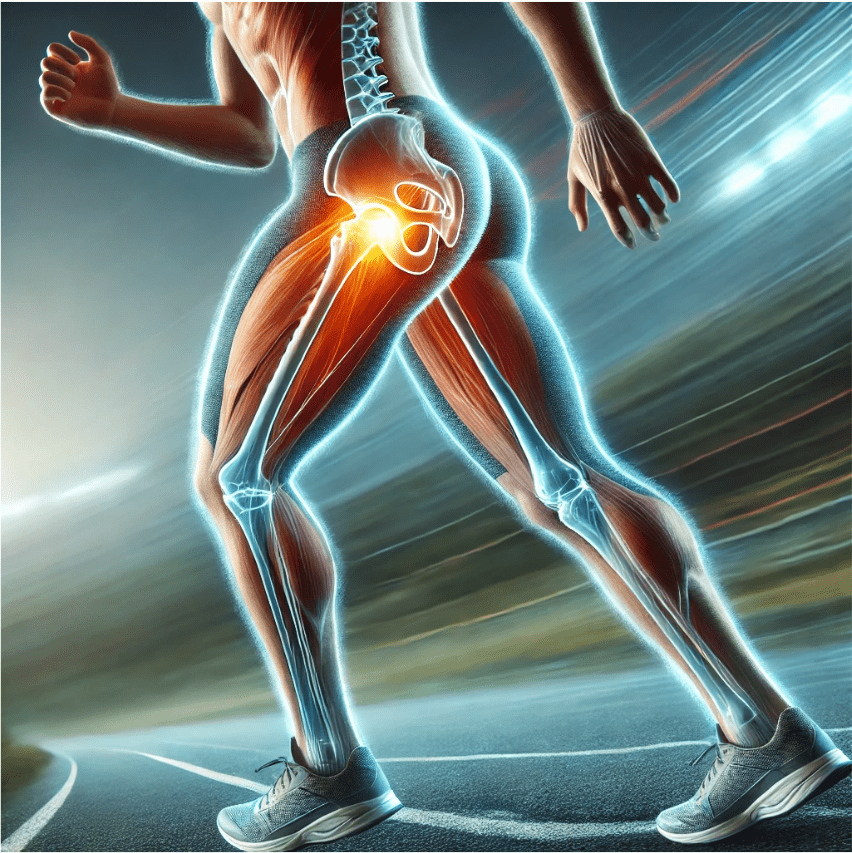

Artrosis de cadera: cómo influye la pisada en su desarrollo

La artrosis de cadera es una de las causas más frecuentes de dolor y limitación de la movilidad en adultos. Aunque muchas veces se asocia a la edad o al desgaste natural, factores como la pisada y la biomecánica del pie tienen un papel clave en su aparición y progresión. En este artículo analizamos cómo […]